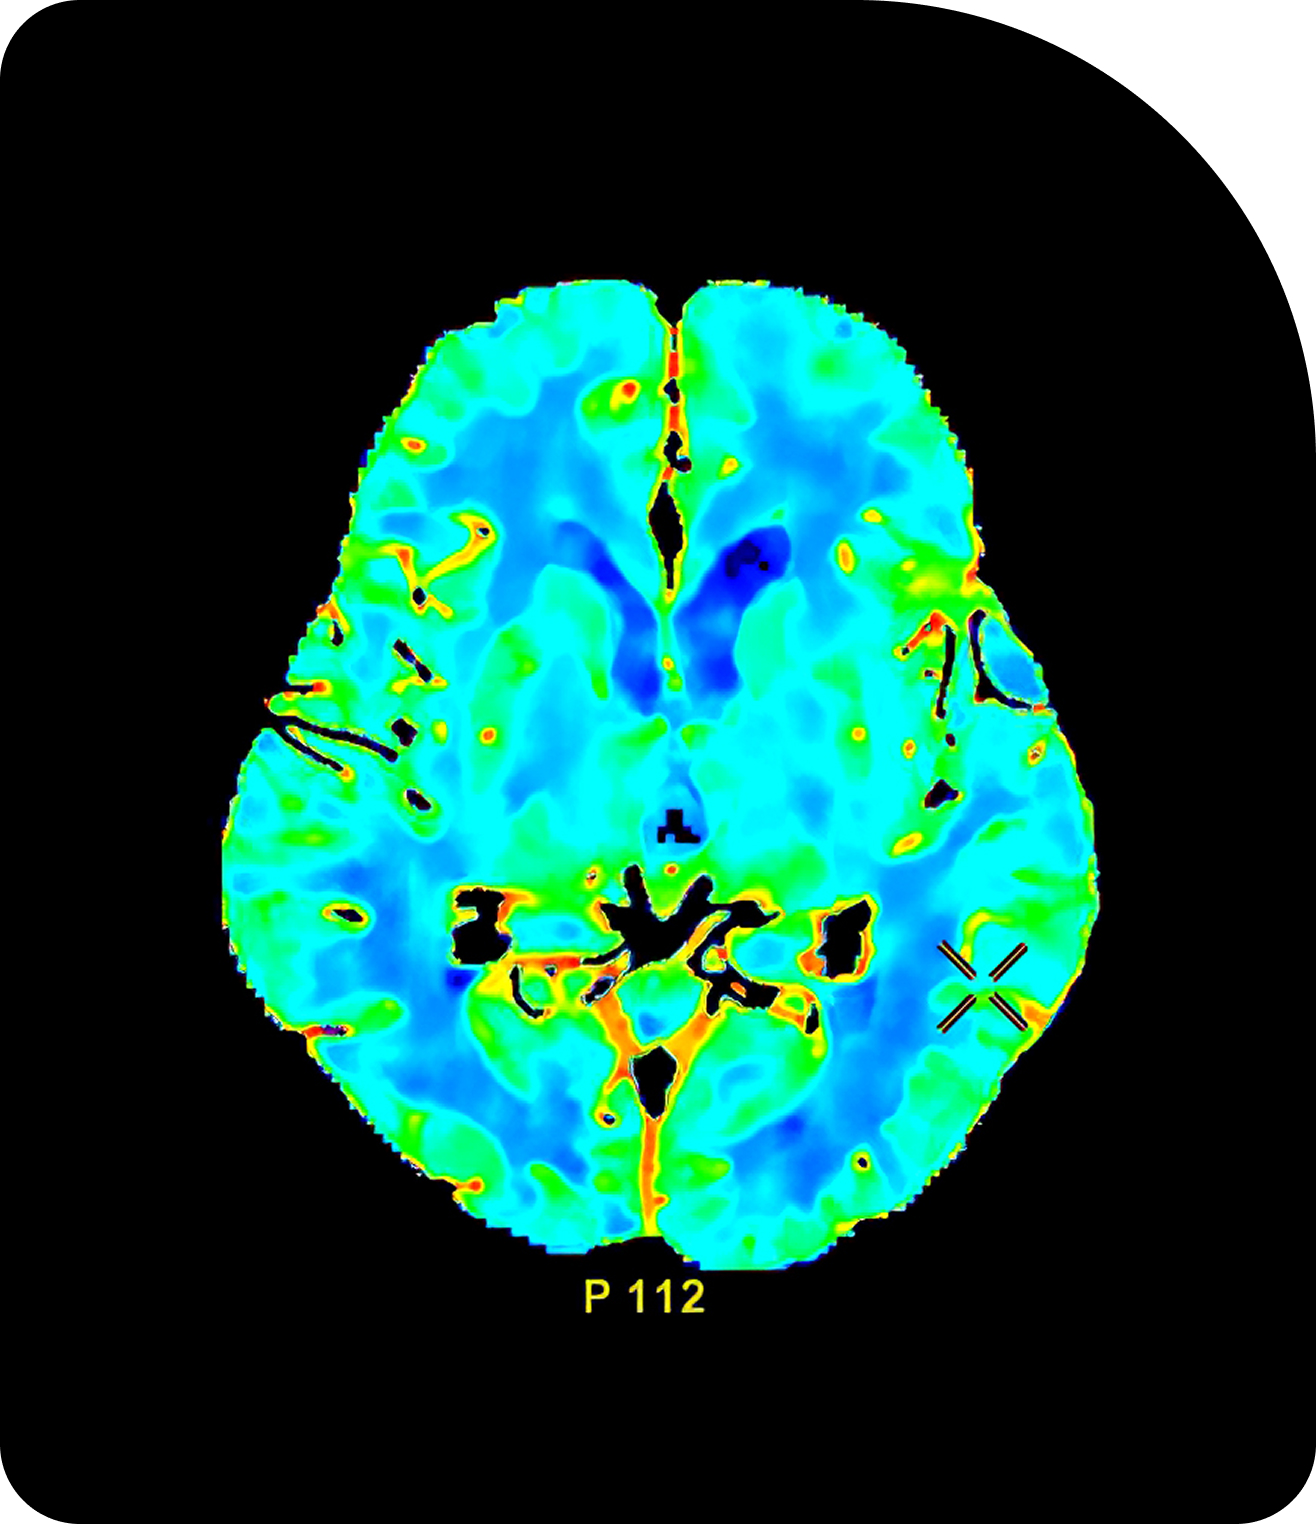

Compare Imaging TechnologiesAdaptive Radiotherapy in Action